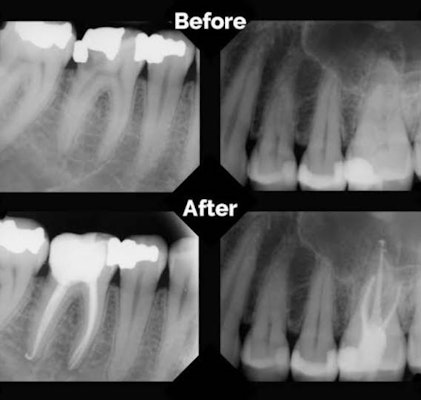

Root canal Signs that you may need a root canal? – Severe tooth pain – Gum swelling – Prolonged sensitivity – Tooth discoloration Why you need a root canal? – An abscess – Tooth fracture – A deep cavity close to the nerve Root canal treatment is often a straightforward procedure to relieve dental pain and save your teeth. It is not more painful than any other regular dental procedure. For the first few days after treatment, your tooth may feel sensitive or discomfort or feel a bit sore. Day by Day, you will start to feel more relief of discomfort.